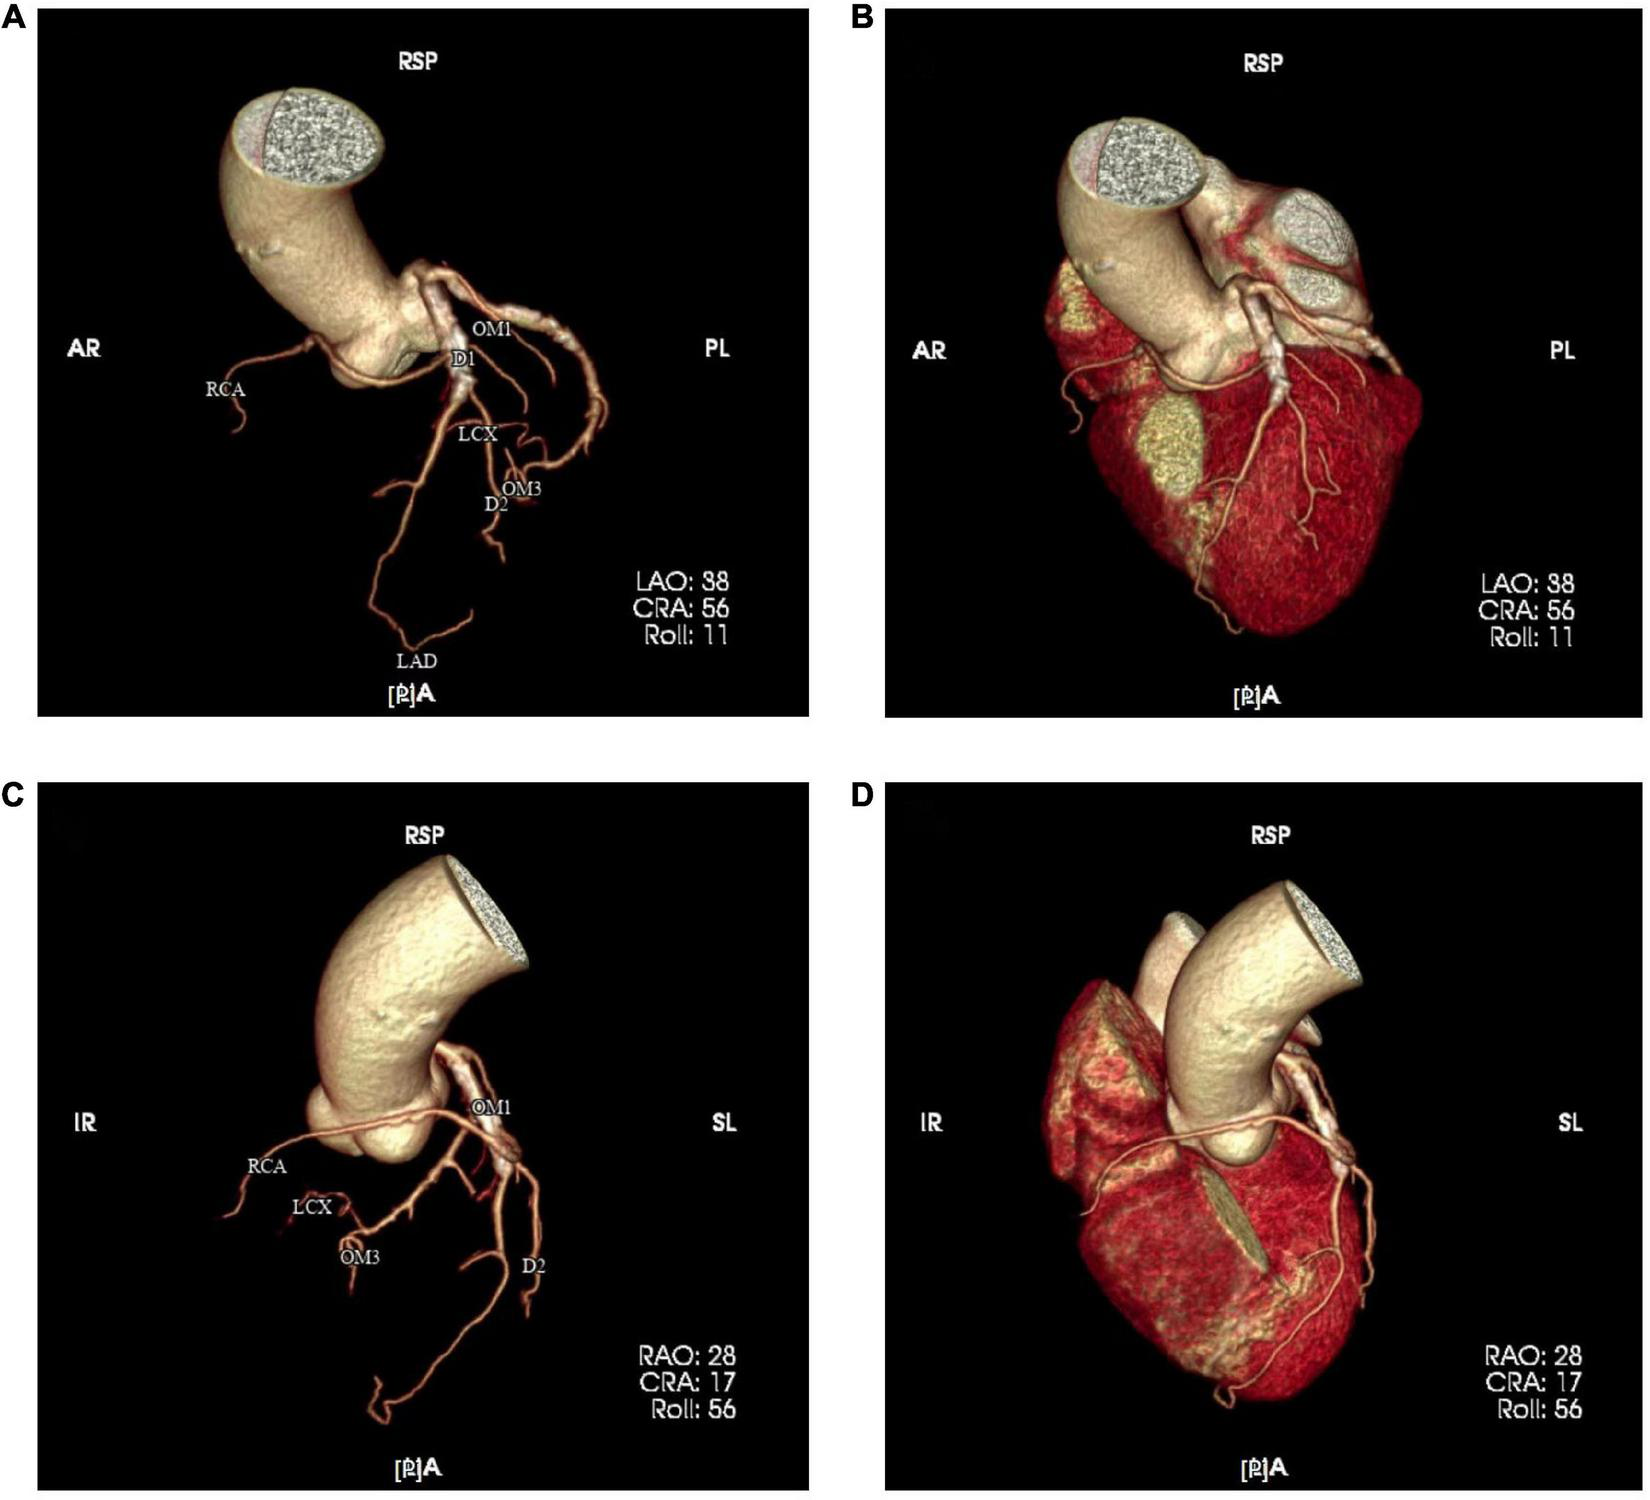

FIGURE 3

Coronary computed tomography angiography (CTA) was re-examined one month after PCI and resulting images (A–D) confirmed the anomalous origin of the right coronary artery.

Four months after discharge, the patient was advised again to undergo coronary angiography, and the results showed complex and severe triple bifurcated lesions, with 90% ostial LAD lesions, 80% ostial D1 lesions, and 70% ostial RCA lesions (Figure 2D). Following coronary angiography, we discussed the revascularization strategy. Two Sion blue wires were passed down the LAD, D1, and anomalous RCA, and two 2.5 × 20 mm drug-coated balloons were deployed in the D1 and RCA (Figures 2E, F). Then, the LAD/RCA/D1 bifurcation was treated with a 3.0 × 36 mm (10 atm) drug-eluting stent (DES) placed in the LAD and two Maverick 2.0 × 20 mm (6 atm) balloons placed in the D1 and RCA (Figure 2G), which were dilated simultaneously for kissing balloon inflation. Then, a proximal optimization technique (POT) was performed with a Quantum Maverick 3.0 × 15 mm high-pressure balloon placed in the LAD. With no symptoms of discomfort, PCI was completed, and the outcomes were satisfactory (Figure 2H). After 3 days, the patient was discharged home on aspirin, ticagrelor, and rosuvastatin. After a 1-month follow-up, we performed computed tomography angiography (CTA) of the coronary artery. Through CTA, we confirmed that the anomalous RCA originated from the middle of the LAD (Figure 3). It passed between the aorta and pulmonary artery in the group of L-II variants (1).